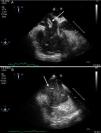

A 44-year-old man was admitted to our ICU due to thoracic trauma with associated bilateral pulmonary contusion. He developed severe refractory respiratory failure (PaO2/FiO2<100) and hemodynamic instability secondary to hypoxemia. Due to the inability to oxygenate the patient, it was decided to begin with veno-venous ECMO therapy. During cannulation of the femoral vein, a large thrombus (white arrow) was observed in the right atrium passing through the tricuspid valve into the pulmonary artery (Fig. 1); suddenly, the patient suffered cardiac arrest in pulseless electrical activity (Fig. 2), requiring advanced CPR maneuvers, recovering spontaneous circulation once ECMO therapy begun (Video). He remained under ECMO for seven days, after which, it was withdrawn due to respiratory improvement. He presented full neurological recovery.